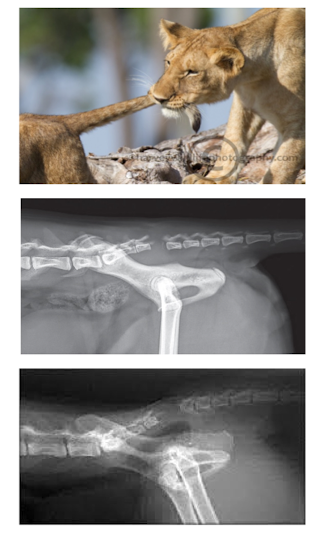

“Tail Pull” injury (cats > dogs)

- traction/avulsion trauma to S1-S3 segments/cauda equina

plantigrade stance, flaccid tail, u/d incontinence, absent anal tone